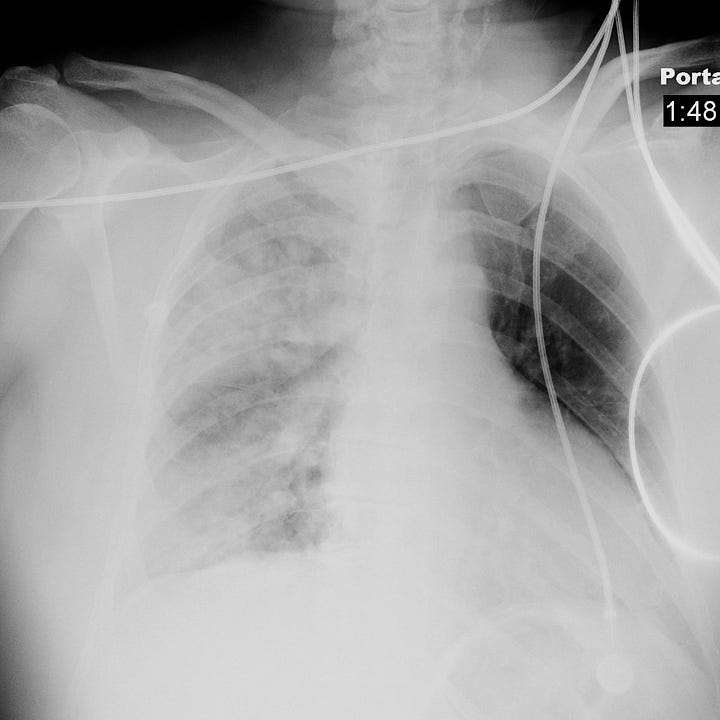

Bronchopneumonia. Heterogeneous airspace opacity predominantly involving the left lower lobe. The lingula is not involved, as the left heart border is sharply visible on the frontal radiograph.